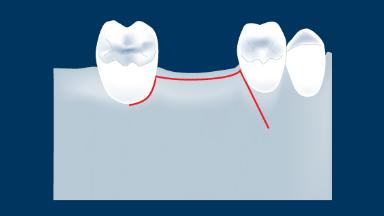

Desenho do Retalho

Vários fatores influenciam o sucesso do tratamento com implantes. Isso inclui requisitos básicos para o aspecto cirúrgico da terapia com implantes. Este módulo se concentrará nos princípios básicos do desenho do retalho para cirurgia oral em geral e para procedimentos cirúrgicos de implante. O objetivo é garantir que a cirurgia possa ser realizada o mais atraumaticamente possível, com visibilidade e acesso adequados à área cirúrgica.

- descrever os princípios desenho do retalho

- descrever os princípios desenho do retalho para cirurgia de implante

- descrever os princípios desenho do retalho para cirurgia de implante